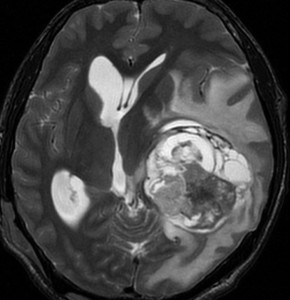

神経線維腫症1型に合併した退形成を示す anaplastic PXA

もともと停止性水頭症があり経過観察を受けていたNF-1の患者さんに発生したものです。嘔気と左片麻痺で発症しました。 開頭手術で亜全摘出(ほぼ全摘)しました。

術後に小さな腫瘍が残っていた(左の画像)ので54Gy/27frの放射線治療をしましたが,無効でした。結局,再開頭手術で残存腫瘍を摘出しました。3年後に同じ部位で再発(中央の画像)したので,また開頭手術で摘出しました。そのまた3年後に同じ部位で再発しました(右側の画像)。この様に,摘出しきれなければ治らないし,摘出できれば治る可能性の高い腫瘍です。腫瘍床での再発は多いものの,転移とか脳深部への浸潤性増殖は少ないといえる腫瘍です。放射線治療が効きにくいということを併せて,atypical meningioma WHO grade 2と似た性格を有しています。